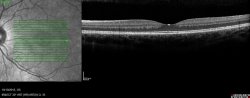

OCT Spectral Domain et Angiographe numérisé HRA SPECTRALIS : une imagerie multimodale.

SPECTRALIS est la combinaison de l’imagerie par balayage laser confocal du fond d’œil et de l’OCT spectral domain.

Cet appareil permet de façon simultanée ou successive :

– l’examen du fond d’oeil ;

– la visualisation de la circulation vasculaire au niveau de la rétine après injection intra-veineuse de différents colorants ;

– la réalisation de coupes de la rétine avec l’obtention d’une image quasi comparable à la réalisation d’une coupe anatomique.

L’analyse des clichés obtenus avec cet appareil permet l’analyse des atteintes de la macula, des vaisseaux rétiniens et du nerf optique, et le suivi sous traitement de ces maladies.

La présence d’un système “eye tracker” permet la réalisation de coupes de grande précision malgré les mouvements oculaires et les clignements.

Exemple clinique de l’intérêt de l’angio-OCT : une dame de 71 ans vient nous voir car sont apparues depuis 1 mois, sur son œil droit, des déformations gênantes à la lecture.

OCT Spectral Domain : y a-t-il un néovaisseau choroïdien actif ?

L’angiographie à la fluorescéine et au vert d’indocyanine ne nous permet pas de trancher de façon évidente, Devant ce doute diagnostic, faut-il lui imposer un traitement lourd par injections à notre patiente ? Ou faut-il la reconvoquer dans 2-3 mois au risque de la revoir avec une perte de vision plus importante ?

L’angio-OCT met en évidence un néovaisseau choroïdien actif car le flux est évident. Nous lui proposons sereinement un traitement par injections intra-vitréennes d’anti-VEGF qui lui permettra de conserver au mieux sa vision.